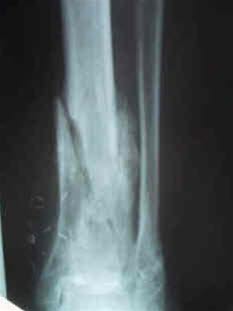

Osteomyelitt nederst i leggbeinet.Osteomyelitt er en bakterieinfeksjon (betennelse) i et ben. Hos barn kommer ofte sykdommen brått på, med sykdomsfølelse, feber, frysninger, smerter og ømhet i den knokkelen som er rammet. Små barn kan ha mer diffuse symptomer og tegn. Nedsatt bruk av en arm eller et bein uten forutgående skade kan skyldes osteomyelitt. Også voksne kan ha et mer snikende sykdomsbilde uten så typiske symptomer.